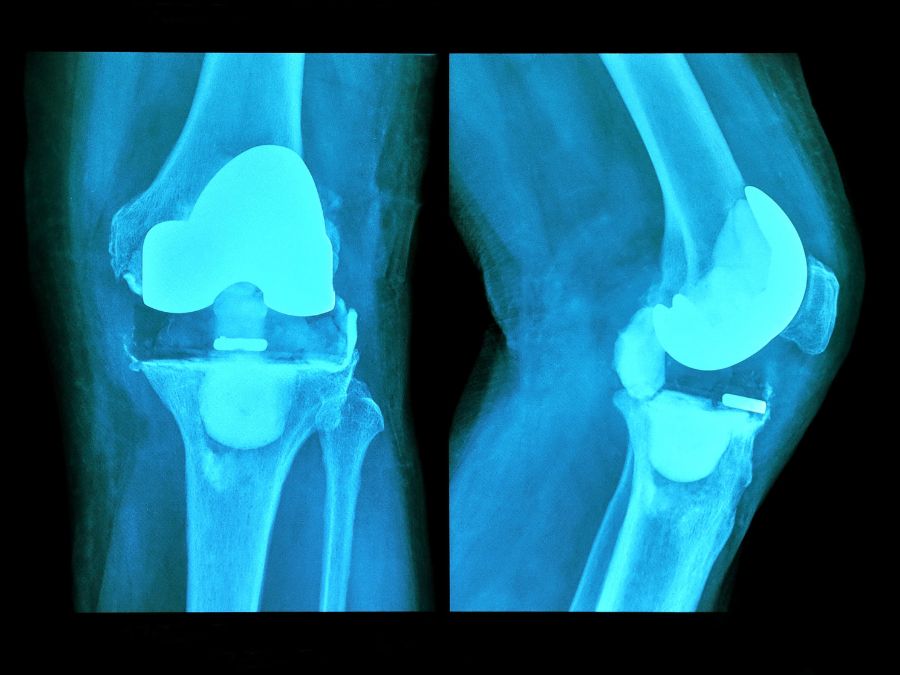

- Radiografie per analizzare il posizionamento della protesi e la qualità dell’osso.

- TAC utile per valutare con precisione difetti ossei e integrazione delle componenti protesiche.

- Impianto della nuova protesi: spesso vengono utilizzati steli più lunghi e componenti rinforzati per migliorare la stabilità.

La sostituzione primaria del ginocchio è generalmente più lineare, mentre la revisione richiede più tempo (2-3 ore o più), strumenti specifici e impianti di dimensioni diverse. Un’altra differenza riguarda lo stato dell’osso e dei tessuti. Dopo anni, possono essere presenti difetti ossei o legamenti indeboliti, che rendono necessario l’utilizzo di protesi più grandi e stabili.